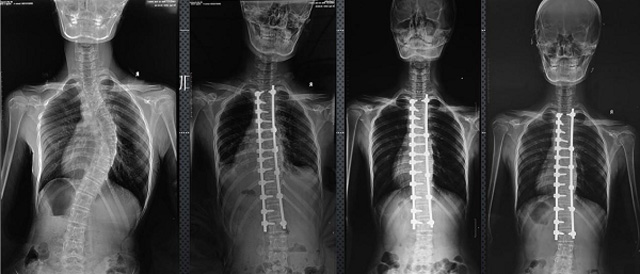

(7)全身拼接功能對有較大尺寸全脊柱拼接圖接桂成金下股分成幾次拍攝,再經(jīng)過秋件開在骨科開展的全脊柱畸形矯治工作中,雖然CT. MRI也能獲取全脊柱影像,接圖像,以便于長度、角度、力線等測量和察脊柱在重力情況下但不能進行立位檢查,無法觀全景觀察。全身拼接功能是高等級DR攝取患者立位全下的功能狀態(tài)圖像,因此采用動態(tài)醫(yī)院特別看重的動態(tài)DR功能之一。注:圖中Cobb脊柱正側(cè)位圖像是首選的檢查方法角度的大小是反映側(cè)彎嚴(yán)重程度的一個標(biāo)準(zhǔn)。